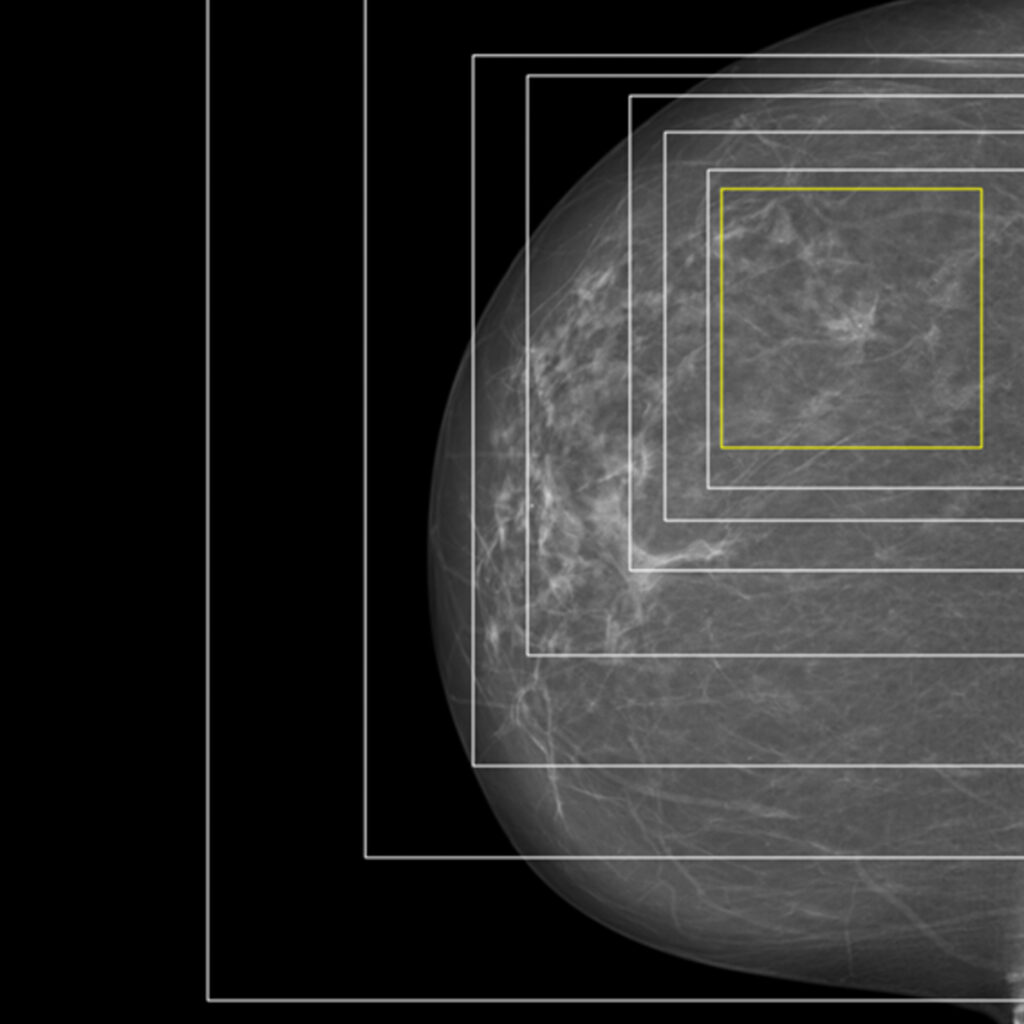

Together with the Cancer Registry of Norway, we are creating analytical methods for mammograms. By using explainable artificial intelligence, we can highlight the areas of an image where a cancerous tumour is located, providing both insight and support for further medical assessment.